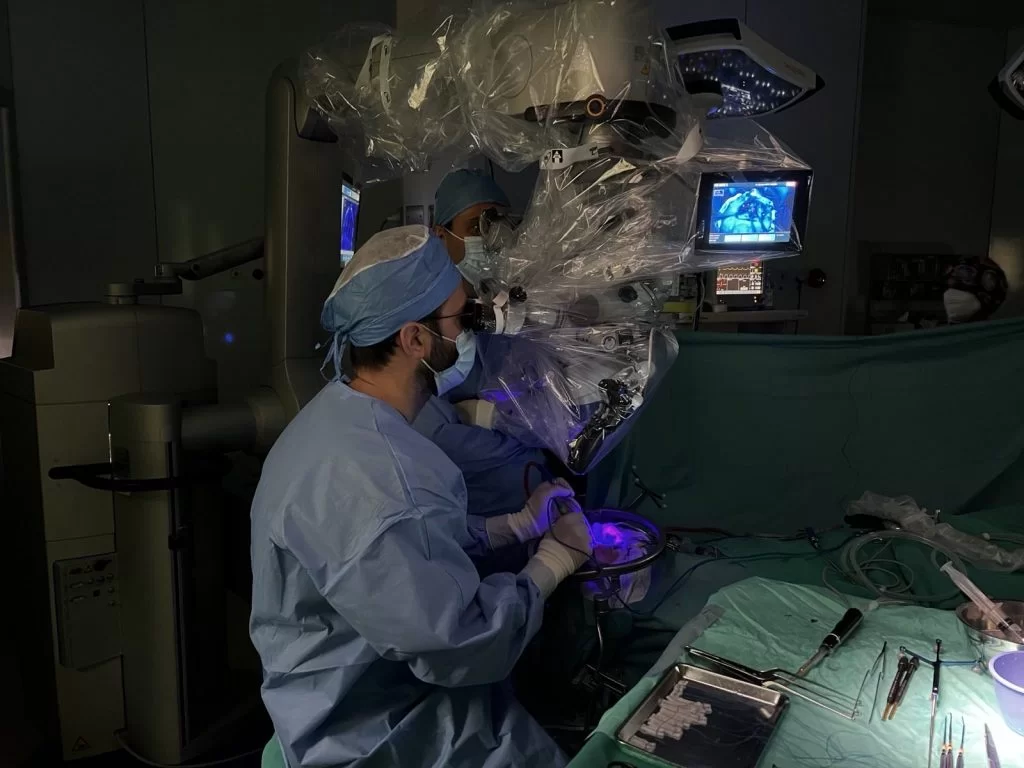

Ο ασθενής υπεβλήθη σε δεξιά κροταφική κρανιοτομία με τη βοήθεια νευροπλοηγού και διεγχειρητικού υπερήχου, νευροφυσιολογικού ελέγχου και διεγχειρητικού ανοσοφθορισμού με 5-ALA.

Στο συγκεκριμένο περιστατικό συνδυάστηκαν πολλές σύγχρονες τεχνικές και τεχνολογίες προκειμένω να επιτευχθεί η πλήρης αφαίρεση του όγκου αλλά και η νευρολογική ακεραιότητα του ασθενούς.

Διεγχειρητικά χρησιμοποιήθηκε ο συνδυασμός νευροπλοήγησης με υπέρηχο. Η χρήση του υπερήχου απαιτεί ειδική εκπαίδευση, δίνει όμως στον χειρουργό τη δυνατότητα να ελέγχει συνεχώς που ακριβώς βρίσκεται και πόσο υπόλειμμα όγκου έχει μείνει. Επιπλέον, χρησιμοποιήθηκε νευροφυσιολογικός έλεγχος, δηλαδή με τη βοήθεια ηλεκτρικής διέγερσης εντοπίστηκε η θέση των κέντρων ελέγχου του εγκεφάλου αλλά και η θέση των νευρικών δεματίων. Τέλος, ο διεγχειρητικός ανοσοφθορισμός με 5-ALA μας επέτρεψε να αναγνωρίσουμε εστίες όγκου οι οποίες δεν ήταν ευδιάκριτες με τη χρήση του μικροσκοπίου και του “απλού” φωτισμού.